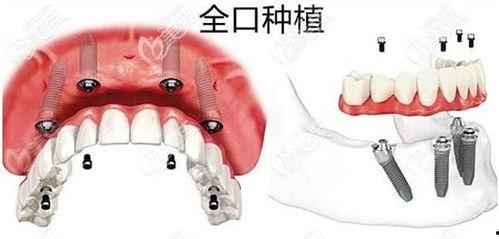

对于这起事件,口腔医学专家表示,种植牙作为一种常见的牙齿修复方式,确实存在一定的风险。虽然种植牙的成功率较高,但术后并发症也是不可避免的。

专家指出,种植牙术后可能会出现疼痛、感染、松动等问题。这主要是因为手术过程中,医生的技术水平、手术器械的消毒程度以及术后护理等因素都会影响到种植牙的成功率。

面对种植牙术后可能出现的问题,患者应该如何维权呢?专家建议,患者在选择口腔医院时,要尽量选择正规、有资质的医院。在手术前,要详细了解手术过程、术后注意事项以及可能出现的风险。